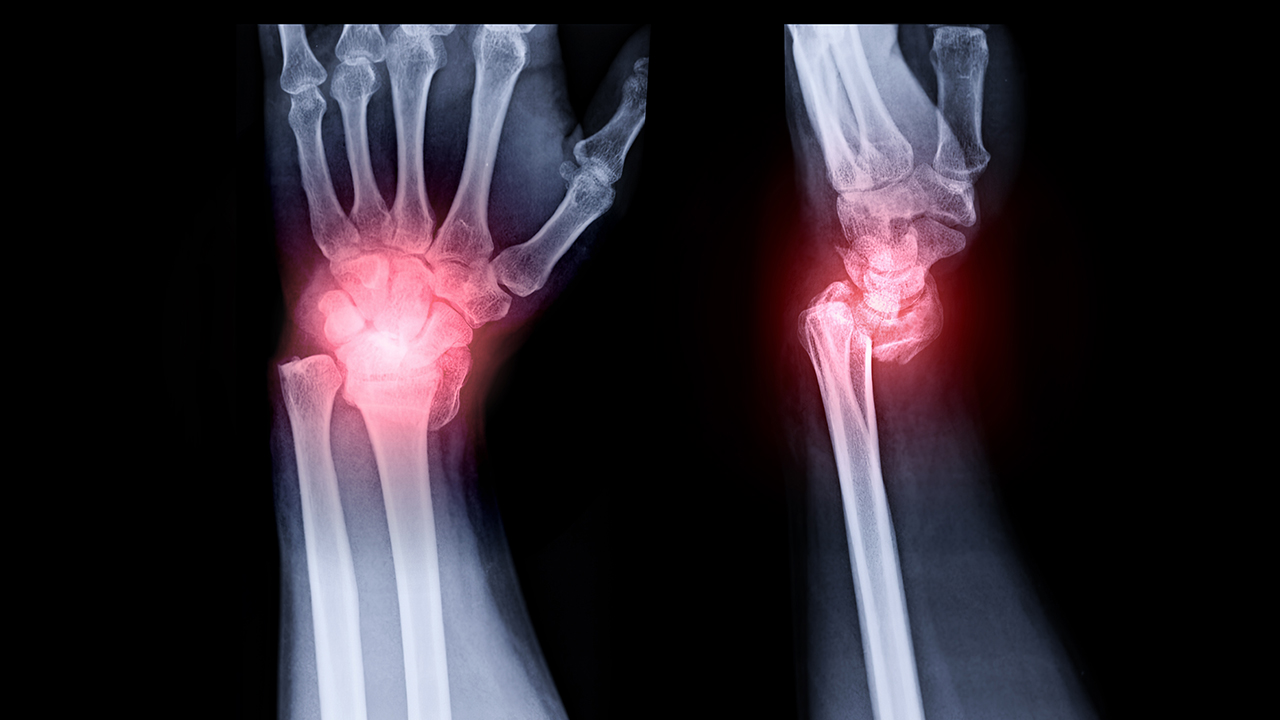

类风湿一般是指类风湿性关节炎。如果患者出现关节炎好几年的情况,并且怀疑为类风湿性关节炎时,可以通过日常护理、物理治疗、药物治疗等方式进行处理。